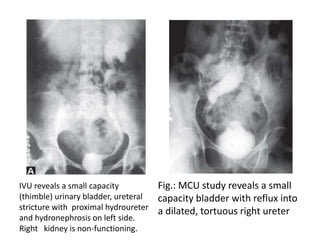

Fig.: MCU study reveals a small

capacity bladder with reflux into

a dilated, tortuous right ureter

IVU reveals a small capacity

(thimble) urinary bladder, ureteral

stricture with proximal hydroureter

and hydronephrosis on left side.

Right kidney is non-functioning.